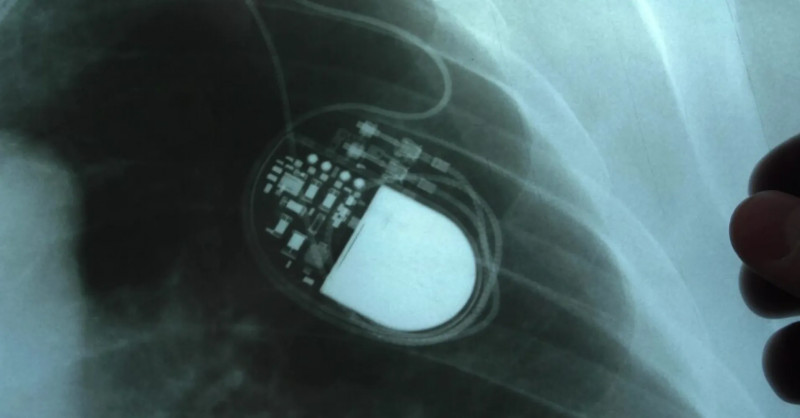

Ministerstvo zdravotnictví podalo trestní oznámení na Fakultní nemocnici Olomouc kvůli podezření z obcházení indikačních kritérií při implantaci kardioverterů-defibrilátorů, což může vést k podvodu a těžkému ublížení na zdraví stovek pacientů. #zdravotnictví #defibrilátory #vyšetřování

Ministerstvo zdravotnictví (MZd) podalo trestní oznámení kvůli operacím pacientů s přístroji na kontrolu srdečního rytmu, takzvaných kardioverterů-defibrilátorů, ve Fakultní nemocnici Olomouc (FNO).

Ministerstvo zdravotnictví podalo trestní oznámení kvůli podezřelým operacím s implantacemi kardioverterů-defibrilátorů ve Fakultní nemocnici Olomouc, což vyvolalo policejní vyšetřování zaměřené na možné obcházení indikačních kritérií a těžké ublížení na zdraví stovek pacientů. #Zdravotnictví #TrestníOznámení #Defibrilátory

Ministerstvo zdravotnictví podalo trestní oznámení kvůli závažným podezřením na manipulaci s dokumentací a obcházení kritérií při implantacích defibrilátorů ve Fakultní nemocnici Olomouc, na což jako první upozornily Seznam Zprávy v loňském prosinci. #zdravotnictví #defibrilátory #bezpečnostpacientů

Ministerstvo zdravotnictví označilo situaci s implantacemi defibrilátorů ve Fakultní nemocnci Olomouc za velmi závažnou a podalo trestní oznámení.

Ministerstvo zdravotnictví podalo trestní oznámení v souvislosti s kauzou defibrilátorů na I. interní klinice Fakultní nemocnice Olomouc, kde interní dokumenty naznačují možné obcházení indikačních kritérií a manipulaci se zdravotnickou dokumentací, a to na základě závažných podezření o neoprávněném čerpání prostředků z veřejného zdravotního pojištění. #zdravotnictví #defibrilátory #trestníoznámení

Ministerstvo zdravotnictví v úterý podalo v kauze defibrilátorů trestní oznámení. Interní dokumenty a datové podklady, které zajistilo, ukazují podle ministerstva na neobvykle vysoké objemy vykazované invazivní péče na I.

Interní audit ve Fakultní nemocnici Olomouc odhalil závažné nesrovnalosti v dokumentaci pacientů zapojených do mezinárodní studie zaměřené na defibrilátory, kdy pouze u dvou z přibližně 70 pacientů byla shoda mezi studijními údaji a nemocničním systémem, a případ nyní vyšetřuje policie pro podezření z podvodu a těžkého ublížení na zdraví. #zdravotnictví #audity #defibrilátory

Loňská interní prověrka v olomoucké fakultní nemocnici odhalila rozsáhlé úpravy dokumentace lidí zařazených do mezinárodní studie o defibrilátorech.

Kardiolog: Podezření, že někomu byly zbytečně implantovány defibrilátory, je děsivé

"Je to děsivé," okomentoval Novinkami oslovený kardiolog podezření, že na 1. interní klinice- kardiologické Fakultní nemocnice v Olomouci (FNOL) byly v minulosti implantovány defibrilátory ICD i pacientům, kteří je nepotřebovali.

Když vás může zabít defibrilátor. Policie v Olomouci prověřuje stovky případů

Kriminalisté zahájili trestní řízení kvůli podezření z těžkého ublížení na zdraví kvůli implantacím defibrilátorů ve Fakultní nemocnici Olomouc, které nebyly potřebné nebo doporučené.

Policie vyšetřuje podezření z těžkého ublížení na zdraví u stovek pacientů s implantovanými defibrilátory